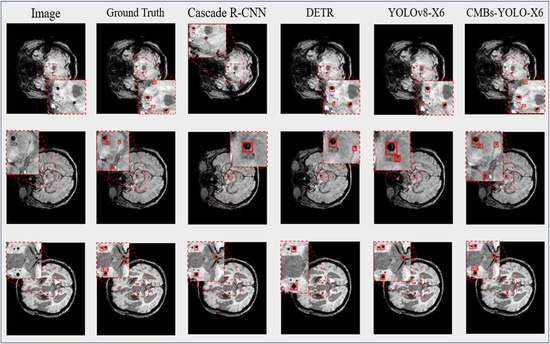

4.3.1. Detection Performance of CMBs

4.3.2. Classification Performance of CMBs